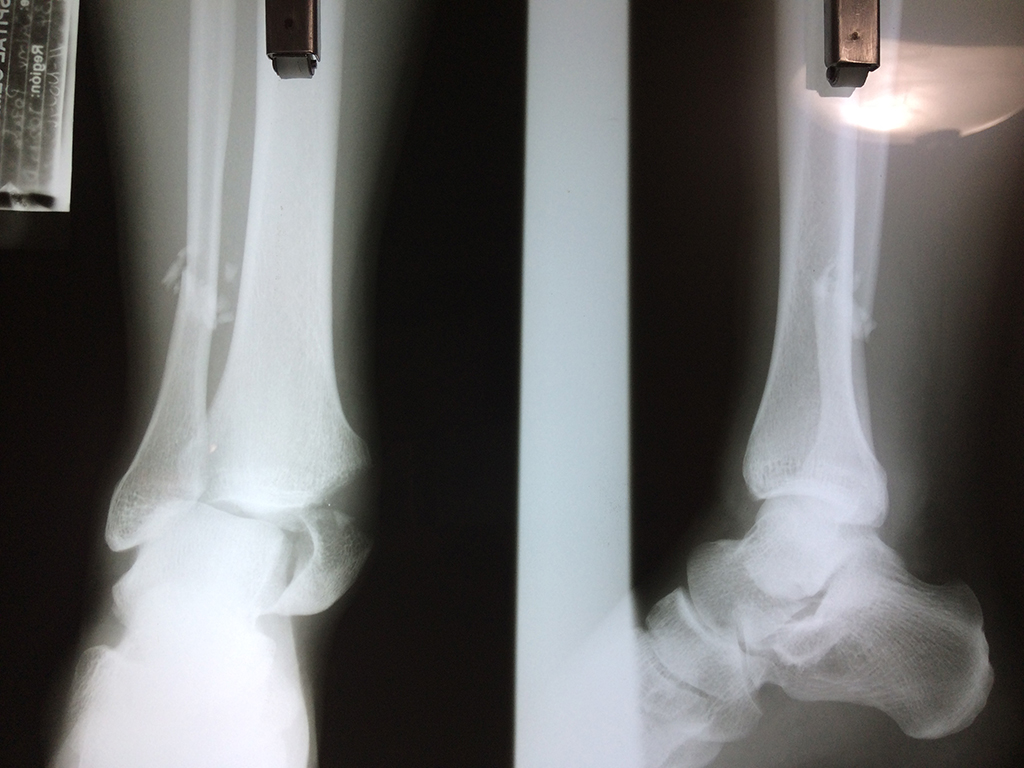

Una fractura de tobillo es la rotura de uno o más de los huesos del tobillo. Estas fracturas pueden ser:

Cuando se necesita cirugía, es probable que esta implique el uso de clavijas de metal, tornillos o placas para sostener los huesos en su lugar mientras la fractura se consolida. Los elementos de soporte pueden ser temporales o permanentes.